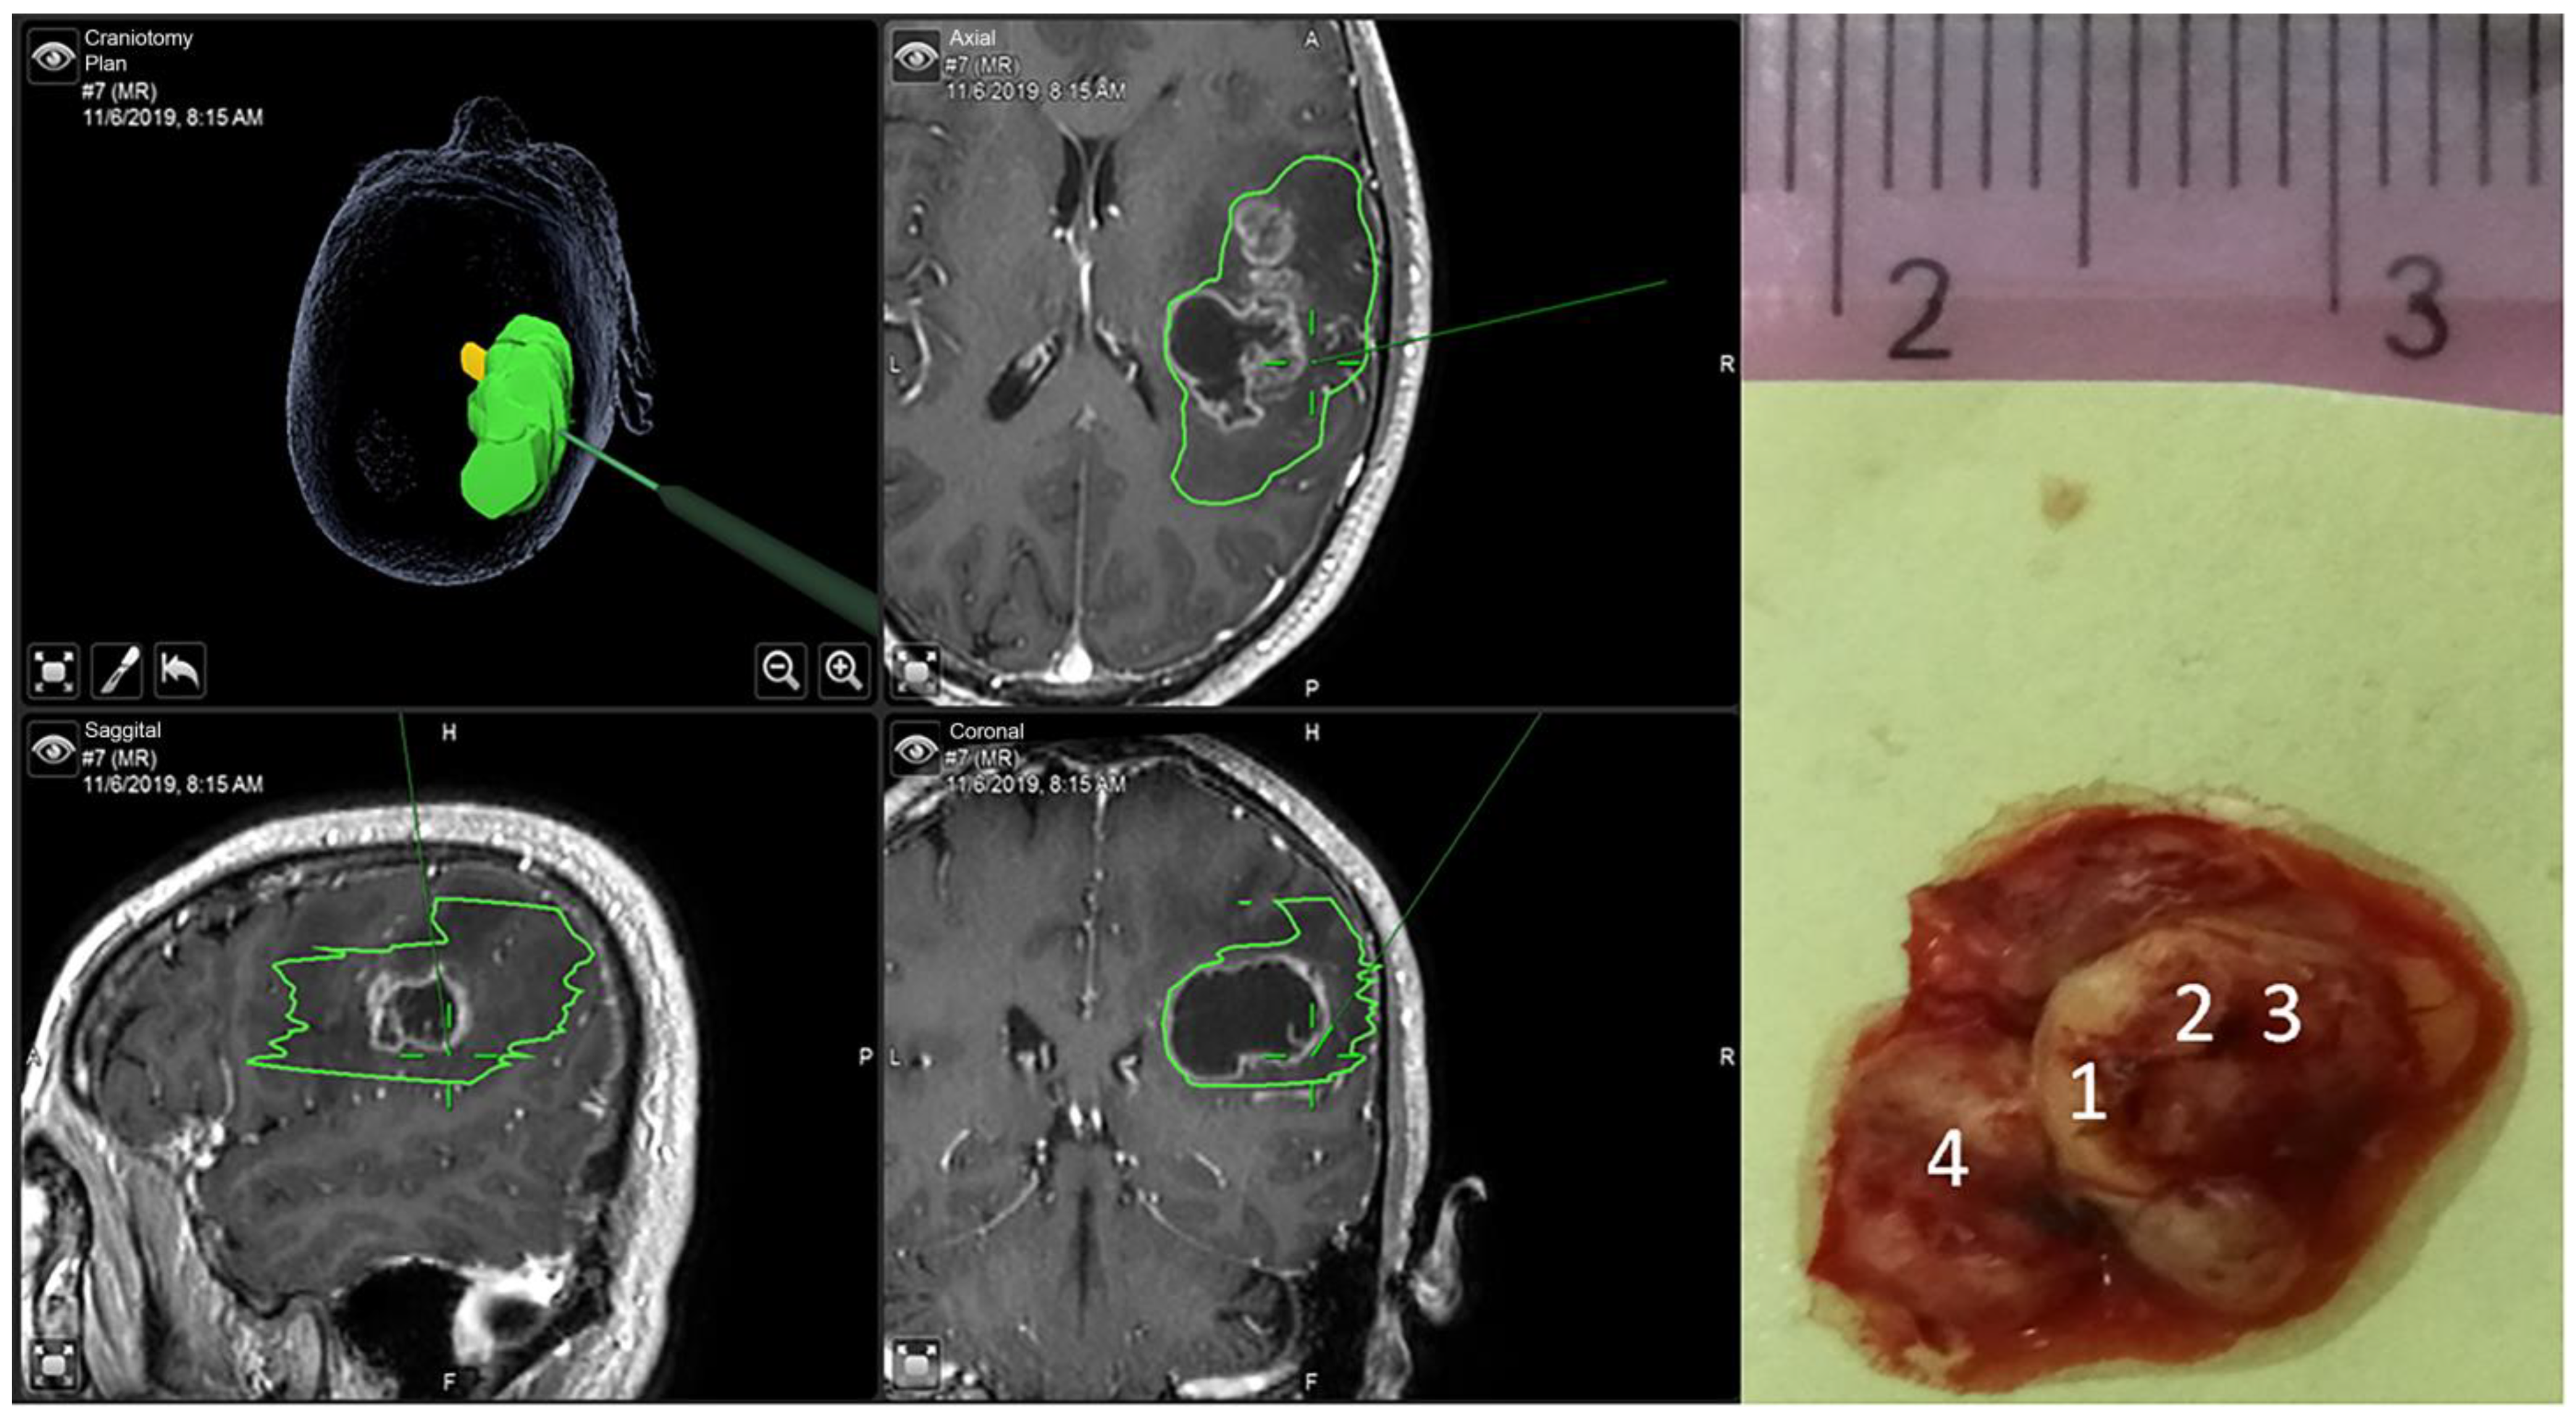

2. Materials and Methods